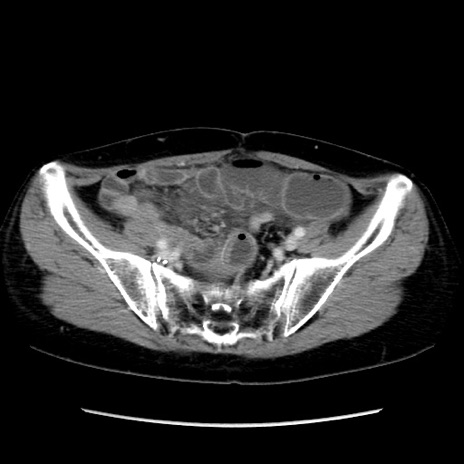

冠状断像

【症例】40歳代 女性

【主訴】上腹部痛、嘔気・嘔吐

【現病歴】約9時間前頃から急に上腹部痛、嘔気、嘔吐が出現。改善しないため救急要請。

【既往歴】子宮頚癌(広汎子宮全摘術、放射線療法)、腸閉塞

【身体所見】腹部:平坦、軟、腸雑音亢進、上腹部を中心に腹部全体に圧痛あり。

【データ】WBC 8400、CRP 0.03